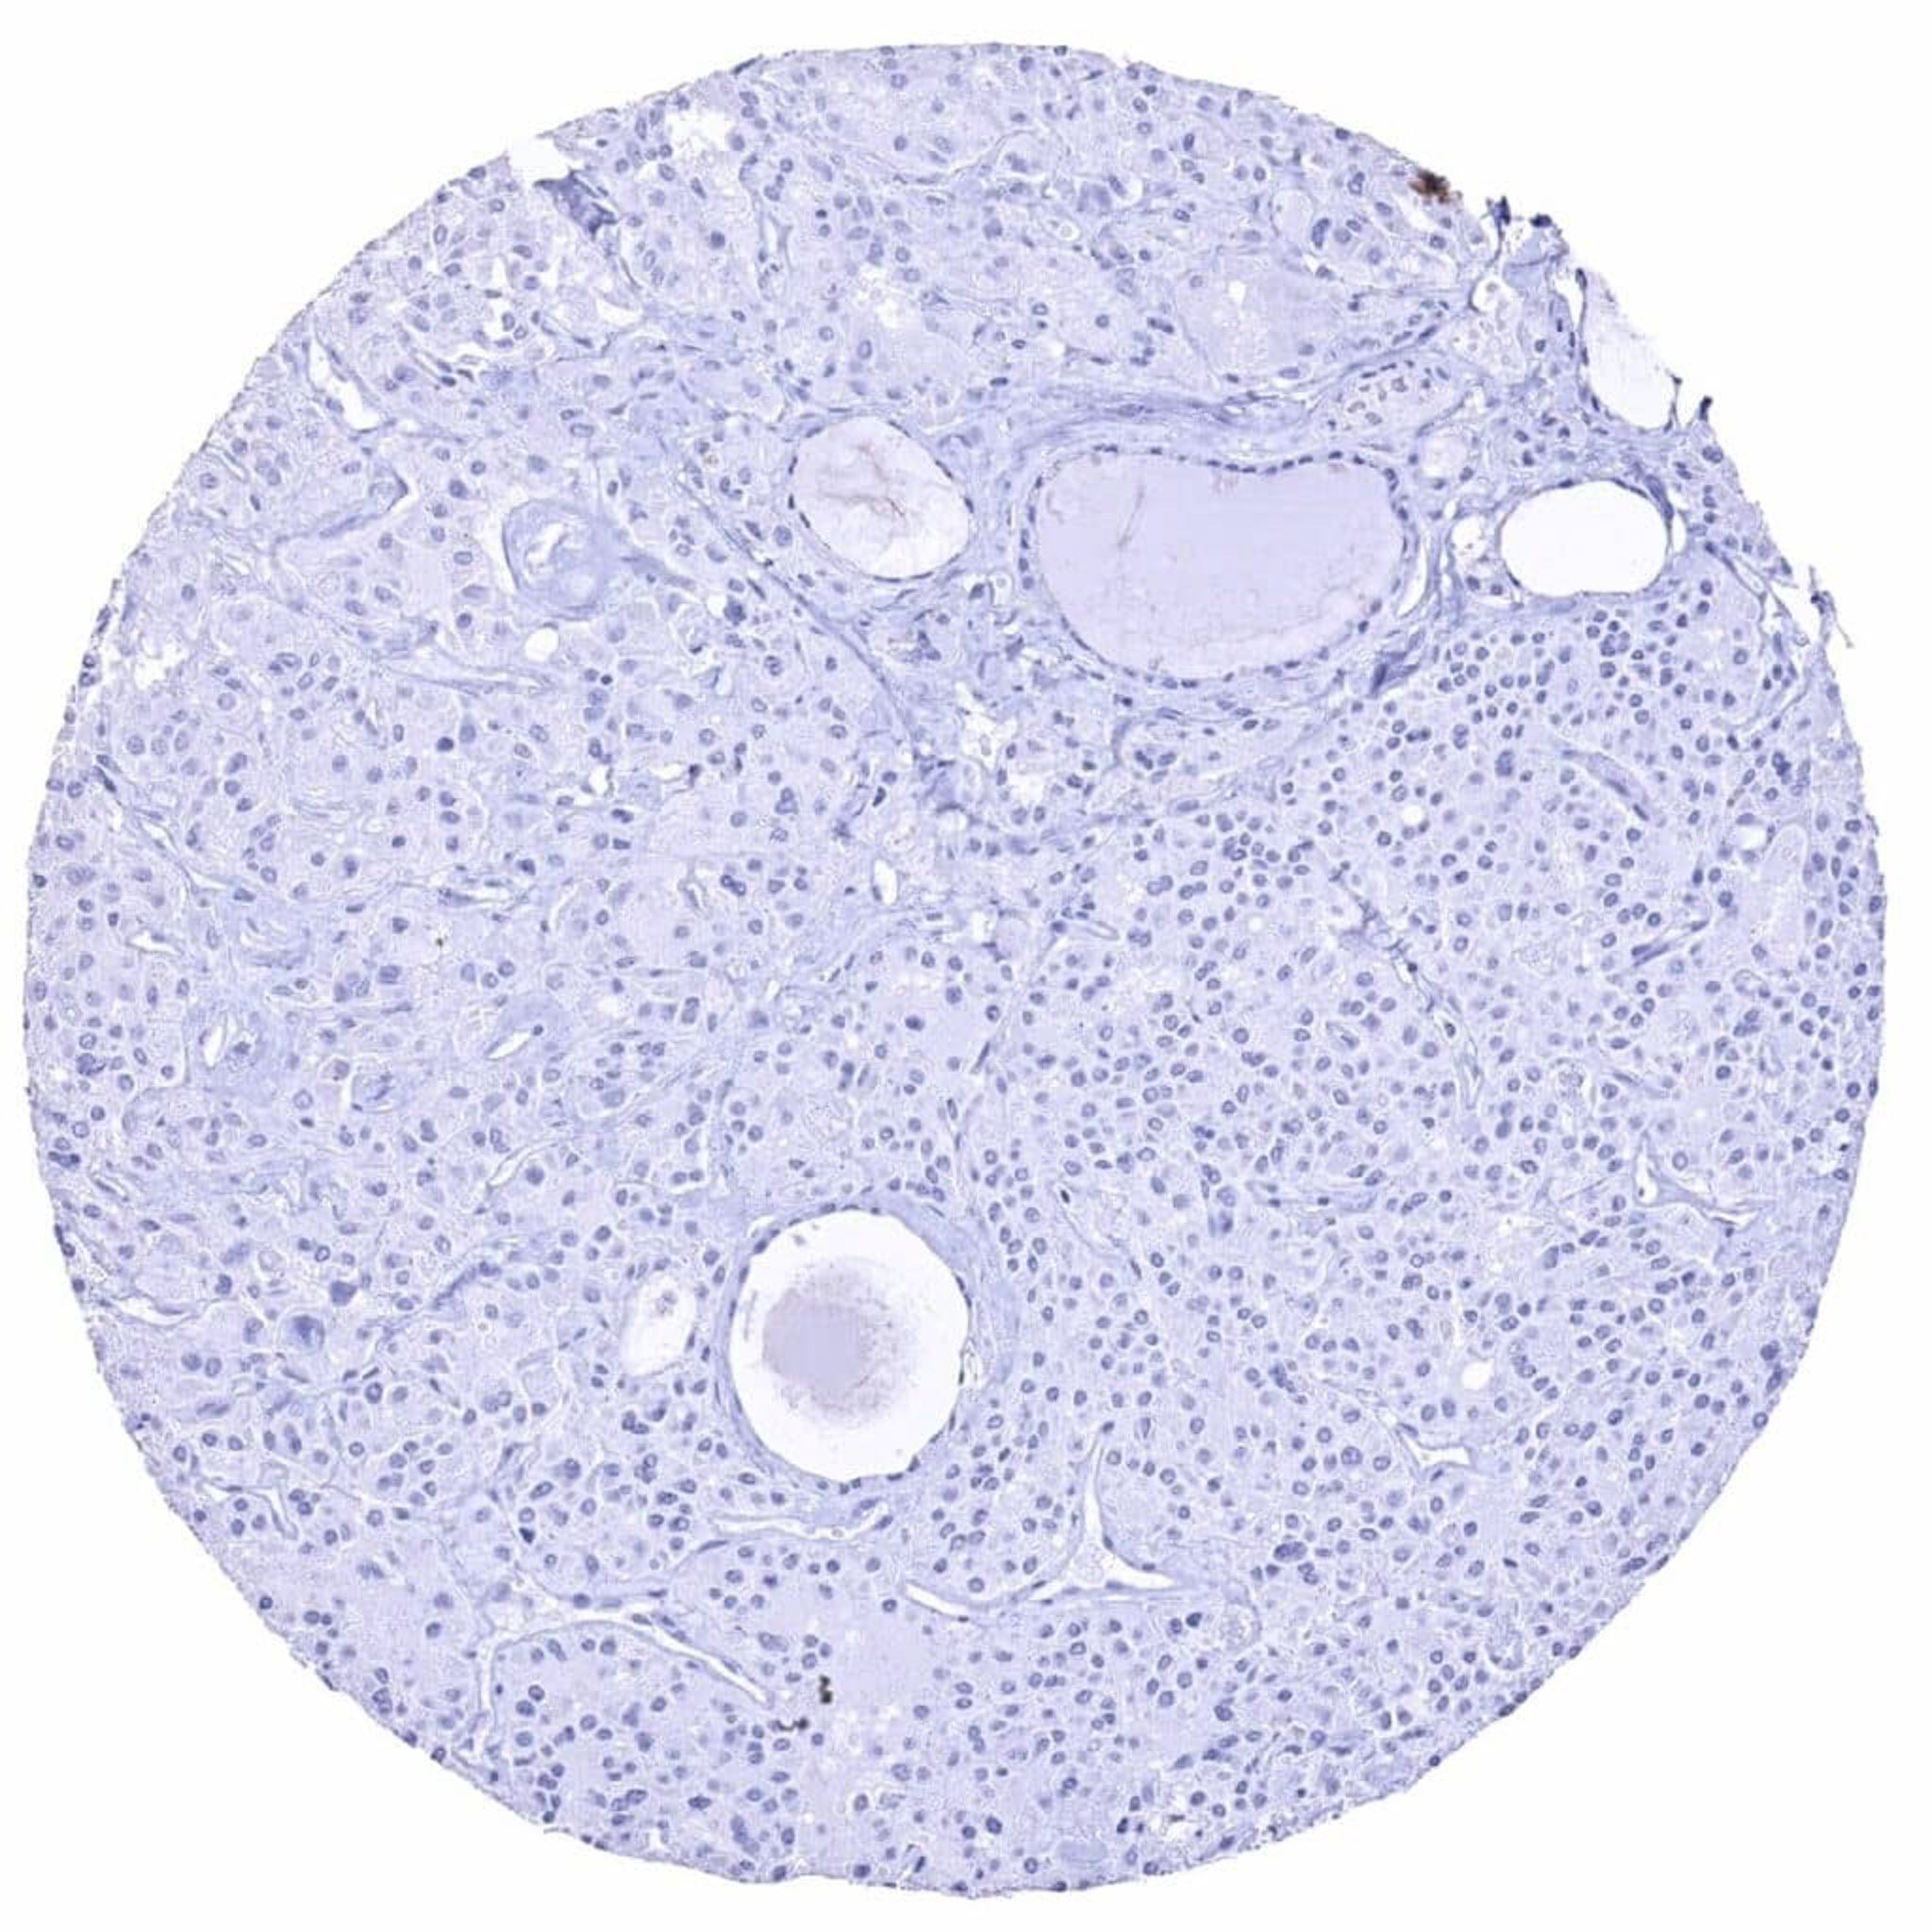

Insulin antibody [HMV308] HistoMAXTM

Ovary – Insulin negative serous high-grade carcinoma